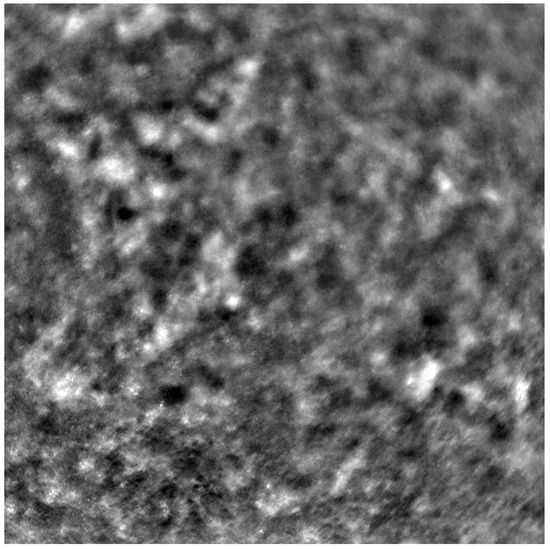

Adaptive optics retinal images depicting a healthy eye, CD, CRD, and STGD are presented in Figure 1, Figure 2, Figure 3 and Figure 4.

Figure 1 depicts the photoreceptor mosaic in a healthy eye. The image is taken paracentrally (2 ° superiorly) due to the limited ability of foveal image acquisition by Rtx™ [17]. By changing the focus point, the quality of an acquired image provides the assessment of photoreceptor parameters in parafoveal cones. The aberration and noise found in Figure 2, Figure 3 and Figure 4 are considered to be the result of poor fixation in eyes with impaired central vision in the course of macular disease. This issue has been addressed in our study. The assessment of factors predisposing for obtaining inadequate image quality was taken into consideration further in this article.

Cone mosaic disruption is an abnormality typical of IRDs. The cone and rod spacing is increased in IRDs compared to healthy retinas [18]. Additionally, poor image quality, likely resulting from inadequate fixation in eyes with low visual acuity, is a problem that, in some cases, makes image acquisition impossible [19,20]. In STGD, as well as in other IRDs, the “dark spaces” depicting areas of disrupted cone structure and abnormal cone reflectance have been described [21,22].

Figure 3. An adaptive optics image of photoreceptors in an eye affected by cone–rod dystrophy (Rtx1™, Imagine Eyes, France). Throughout the image, the cones are not clearly visible. Observe the “dark spaces” scattered within the cone mosaic across various regions of the picture.